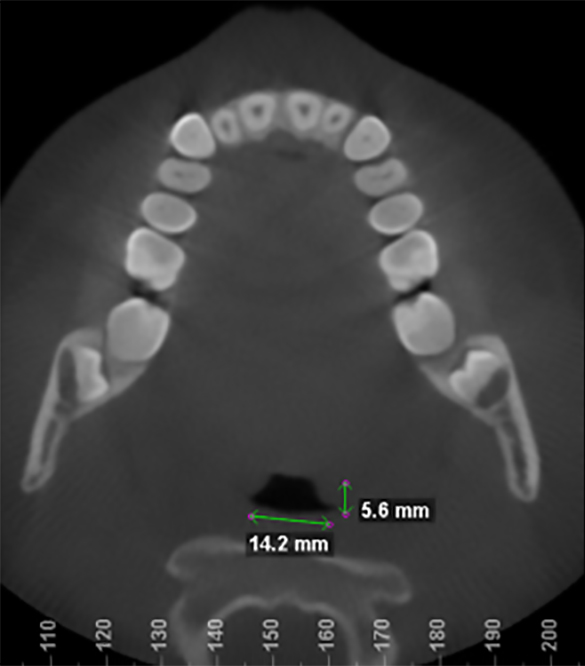

Measurements of upper airway before treatment.

Measurements of upper airway after 9 months.

After 9 months of treatment patient reports sleeping great, no buzzing in the ears, waking refreshed, much more energy during the day, able to bike with nasal breathing. Feels much more room for her tongue in her mouth and significantly improved ability to breathe through her nose.